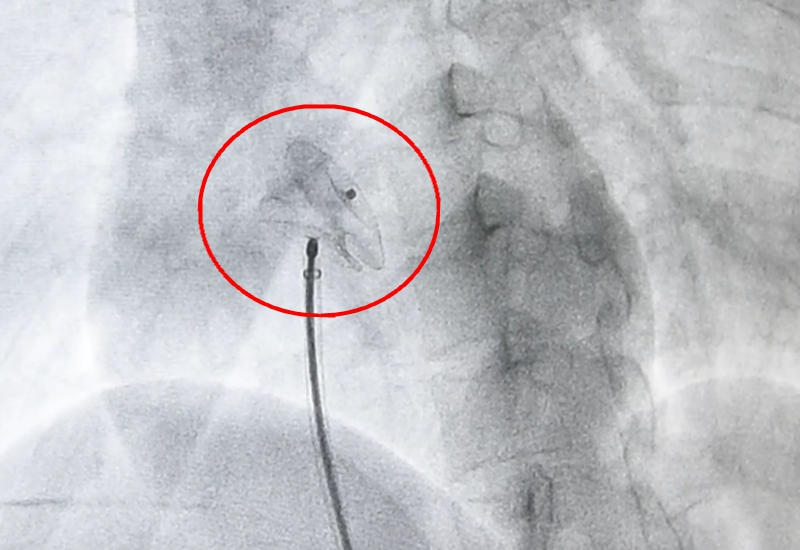

从下肢静脉入口,救心团队利用一根携带封堵器的导丝,循着静脉一路探查,深入心脏内部,抵达缺损部位后,快速释放封堵器。

封堵器犹如一把“工”字型的雨伞,紧紧地卡在房间隔缺损处。术后即刻心超提示,房间隔缺损被完全封堵,左右心房血液分流最终消失!术后第二天,小英便顺利出院。